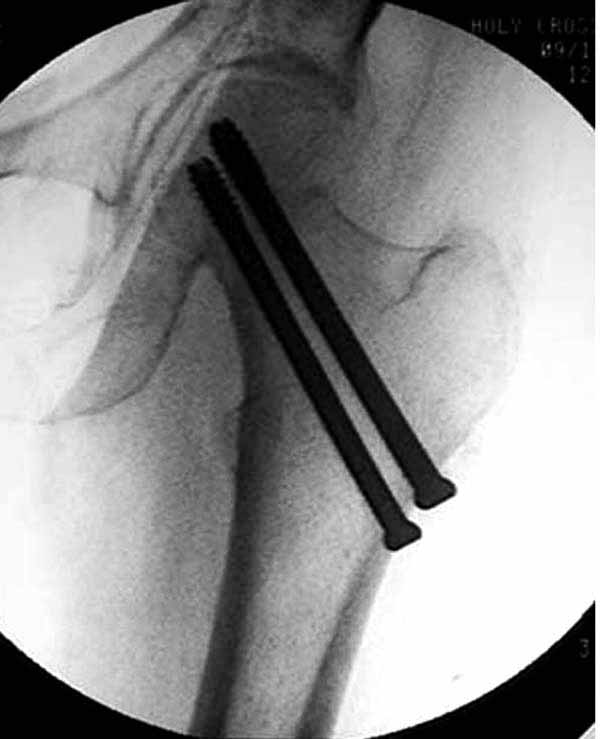

Как отметили коллеги, необходимо обратить внимание на последовательность введения каннюлированных шурупов. Рекомендуется введение в форме “V”, т.е основанием вниз, потому что в другой последовательности за счет увеличения стресса латерального кортекса имеется риск перелома. За редким исключением удается установить Guide wire с первой попытки и многоразовые пробы спицей увеличивают стресс. Небольшая травма может привести к перелому.

Здесь подобный случай, где стрессовый перелом обнаружен через 2 недели после фиксации. Применен Blade Plate с дополнительными шурупами.